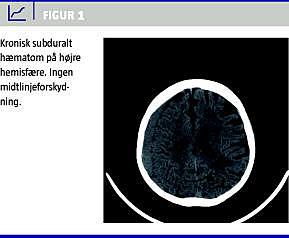

Intrakraniel hæmoragi er en sjælden, men alvorlig blødning hos disse patienter. Den debuterer ofte i form af intracerebral hæmoragi. Kronisk subduralt hæmatom (KSDH) er endnu sjældnere hos patienter med ITP (Figur 1 ).

I litteraturen er der beskrevet ti tilfælde, hvor disse patienter fik KSDH [1-3]. Her beskrives en patient, som fik KSDH to gange med syv måneders interval.